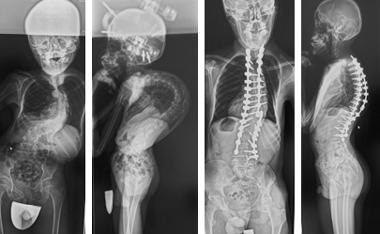

骨切りを併用した後方矯正固定術

せぼねの変形が大きかったり、再手術の場合には癒合してせぼねの骨切りを行い、再度矯正固定を行う場合があります。5時間前後の長時間の手術となります。入院期間は小児患者様で2週間程度、大人の患者様では3週間程度で場合によってはリハビリテーション病院へ転院をして頂き、さらにリハビリテーションを行います。

-

腰椎固定術後後弯に対する椎体骨切り術を併用した後方矯正固定術

こどもの特発性硬膜拡張症に伴う後側弯症に対する後方矯正固定術

前方後方矯正固定術

背骨が大きく変形している場合や再手術の際に前方手術と後方手術を両方行って、せぼねの矯正と固定を行います。1日で両方の手術を行う場合と2日間に分けて手術を行う場合があります。大人の患者様では3週間程度で場合によってはリハビリテーション病院へ転院をして頂き、さらにリハビリテーションを行います。

成人期遺残特発性側弯症に対する前・後方矯正固定術 -

成人脊柱変形に対するLIFを併用した前方後方矯正固定術